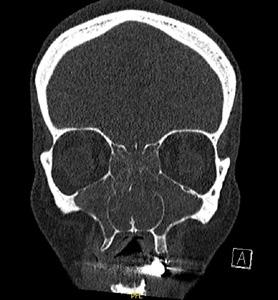

Clear differentiation from other conditions that share similar symptoms of nasal obstruction and rhinorrhoea is also required to ensure correct diagnosis. Chronic sinusitis has overlapping features and should be included in the differential. The smell fibres are located more posteriorly and higher in the nose and consequently smell function is more significantly affected by conditions involving the skull base or nasal sinuses. Thus moderate to severe loss or reduction in smell is more likely to infer a diagnosis of chronic sinusitis or less commonly tumours of the skull base. For the large majority of patients with Allergic rhinitis, smell loss if present is mild or at most moderate in nature and often fluctuates. (Figure below)

Where a diagnosis is unclear or when response to an appropriate INCS is suboptimal, early referral to a specialist should be considered to facilitate nasendoscopic evaluation for diagnosis and escalation of treatment.